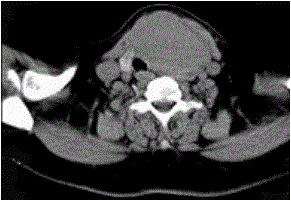

问题 女,56岁,发现颈部肿块30天,颈部肿大,无红肿热痛,无呼吸困难,无吞咽困难,无心悸胸闷烦躁史。近1个月来因肿大不适而来就诊。发病来饮食睡眠正常,体重无下降。如图所示该患者最可能诊断为()

选项 A.甲状舌管囊肿 B.甲状腺乳头状癌 C.甲状腺原发淋巴瘤 D.甲状腺腺瘤 E.甲状腺脓肿

答案 D